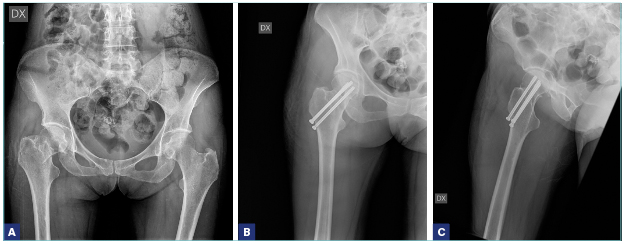

Anche l’età deve essere però un criterio di scelta del trattamento chirurgico. Nei pazienti più giovani (sotto i 60-65 anni) 7, è preferibile evitare l’intervento di protesi, in considerazione del fatto che si tratta nella norma di pazienti più attivi (che quindi sottoporrebbero l’impianto a degli stress maggiori) e che correrebbero il rischio, negli anni a seguire, di sottoporsi, vista la durata non indefinita di una protesi, a una revisione dell’impianto, intervento senza dubbio di maggiore complessità rispetto a un primo impianto. Si preferisce, per questo motivo, tentare di trattare i pazienti più giovani con un intervento di osteosintesi (viti cannulate, mini DHS) anche in caso di frattura mediale, sempre che la frattura sia riducibile 8. Le linee guida della SIOT, in accordo con le evidenze scientifiche maggiori, raccomandano l’osteosintesi anche negli anziani, in caso di fratture mediali composte. Questa scelta di trattamento ha dei pro e dei contro. I vantaggi sono la maggiore rapidità dell’intervento chirurgico, la minor perdita di sangue e l’accorciamento della degenza ospedaliera, tutti fattori che in un soggetto anziano possono essere determinanti nel ridurre le complicanze. Fra gli svantaggi, c’è sempre da considerare la possibile necrosi della testa del femore, che obbligherebbe il paziente a sottoporsi a un secondo intervento chirurgico di conversione della sintesi in protesi (il paziente deve essere adeguatamente informato su questo rischio). Inoltre, dobbiamo considerare la cautela che alcuni chirurghi pongono nelle disposizioni postoperatorie. Infatti, nonostante non ci sia concordia sotto questo aspetto, alcuni ortopedici preferiscono che il paziente operato di osteosintesi con viti eviti il carico per qualche settimana. Questo comporterebbe un rischio di allettamento, mai consigliabile in questa categoria di pazienti. È comunque assolutamente indicata una sintesi con tre viti (non con due) sui tre piani dello spazio, che conferisce maggiore stabilità.

Per quanto riguarda le fratture laterali (basicervicali, pertrocanteriche, sottotrocanteriche), l’indicazione condivisa universalmente è quella a un intervento di osteosintesi, che può essere effettuata con un chiodo-vite, rappresentato da un chiodo endomidollare che si introduce nel canale diafisario del femore e da una vite cefalica, con un angolazione variabile (si introduce nel collo del femore fino alla testa), o con una vite-placca, in cui la sintesi consiste in un sostegno laterale (la placca) più la vite cefalica, anche questa di varia angolazione. Nelle fratture sottotrocanteriche è raccomandato l’uso del chiodo endomidollare di lunghezza variabile in base alle caratteristiche e alla sede della frattura.

Le complicazioni tardive spesso aggravano ulteriormente un quadro clinico già di per se complesso in un paziente anziano: Il cut-out o il cut-through della vite cefalica, la pseudoartrosi, la rottura dei mezzi di sintesi, la necrosi avascolare della testa del femore e più raramente le fratture diafisarie possono verificarsi a causa di una combinazione e di fattori come quelli già citati legati alla frattura, quelli legati al trattamento scelto e alla tecnica chirurgica 10.